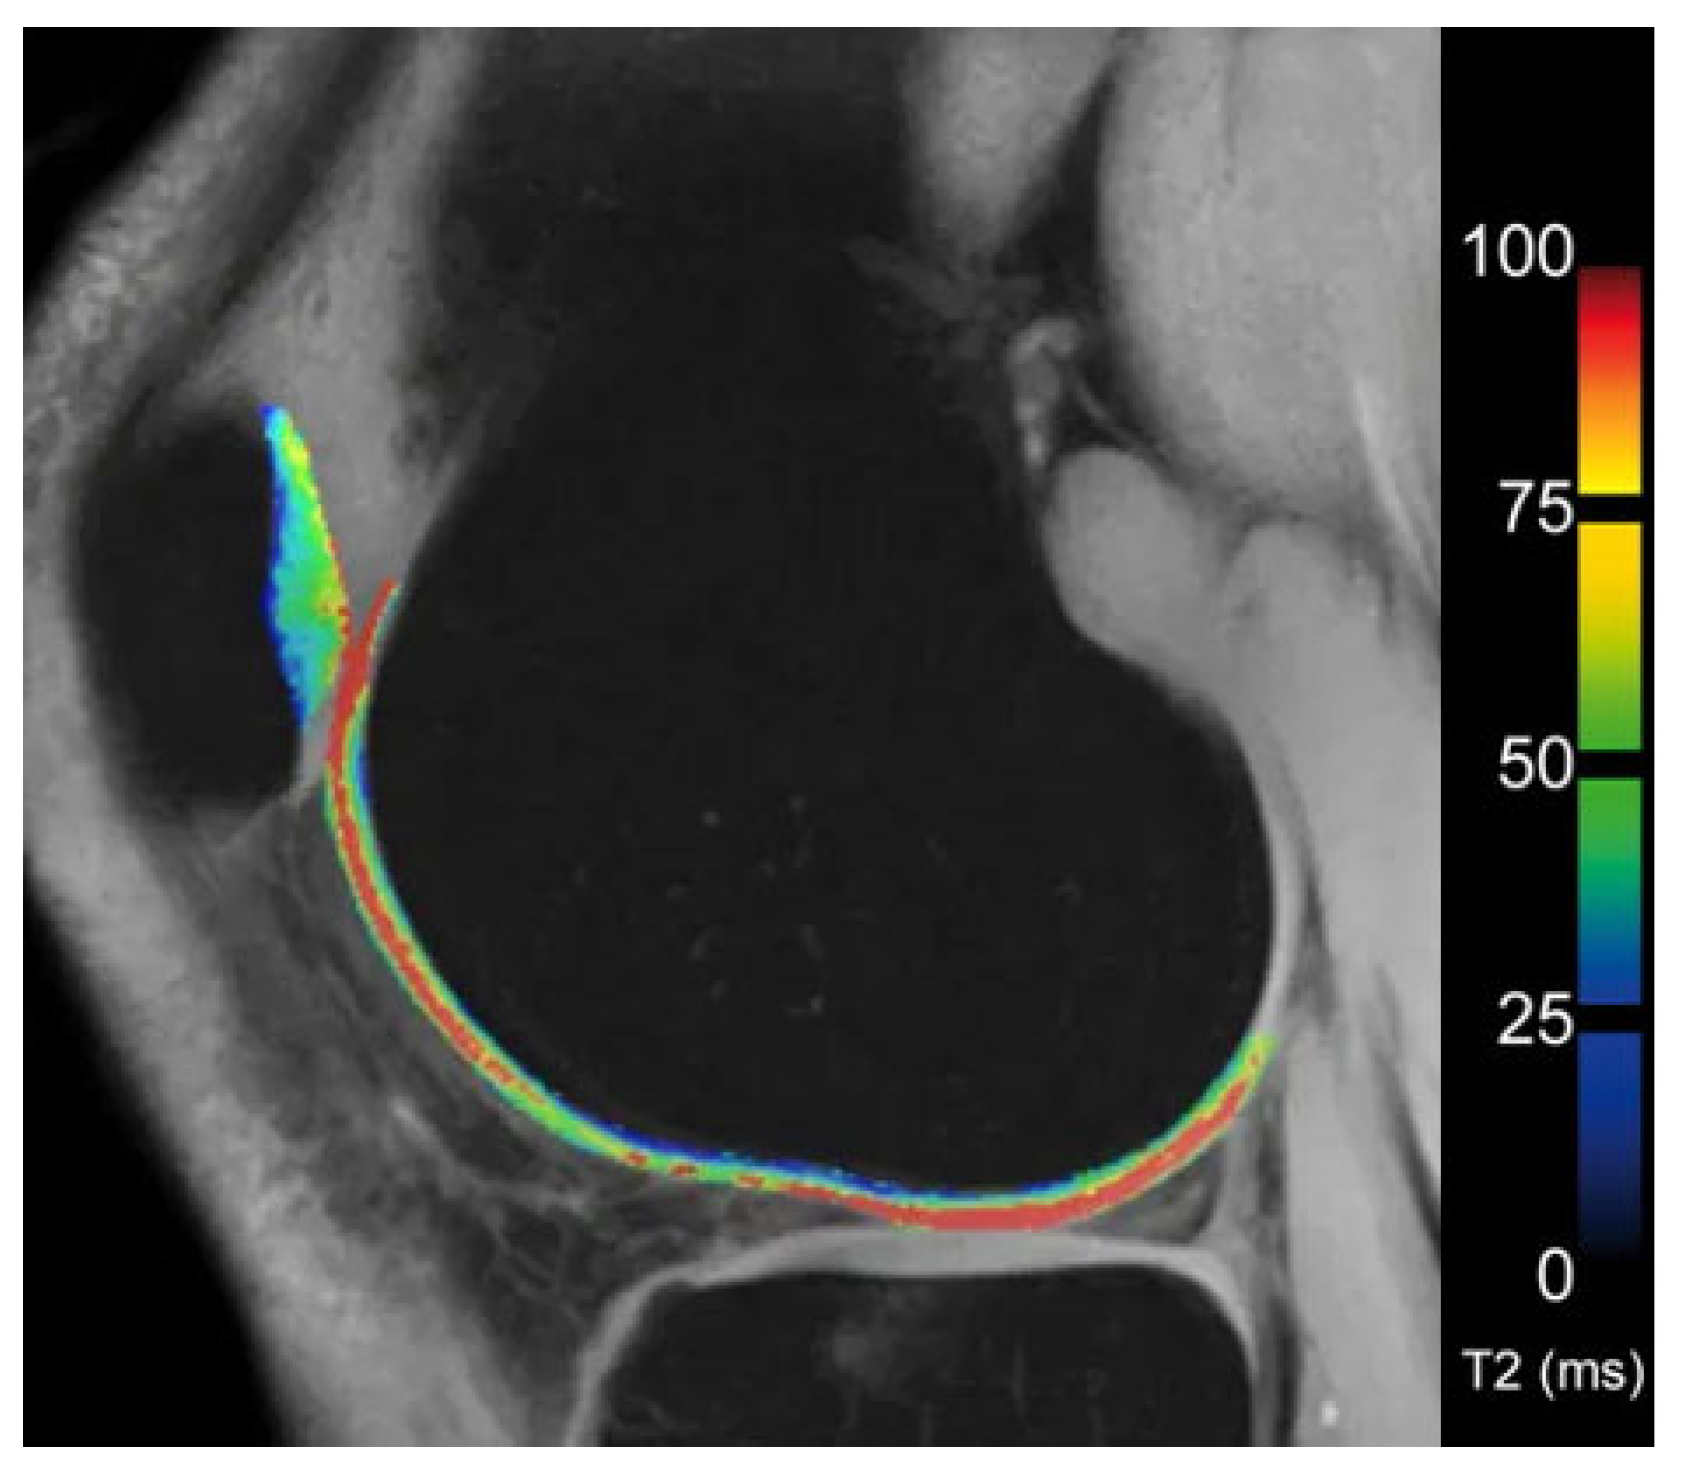

6.3. T2 Mapping

- Dunn, T.C.; Lu, Y.; Jin, H.; Ries, M.D.; Majumdar, S.; Roemer, F.W.; Demehri, S.; Omoumi, P.; Link, T.M.; Kijowski, R.; et al. T2 Relaxation Time of Cartilage at MR Imaging: Comparison with Severity of Knee Osteoarthritis. Radiology 2004, 232, 592–598. [Google Scholar] [CrossRef]

- Koff, M.; Amrami, K.; Kaufman, K. Clinical evaluation of T2 values of patellar cartilage in patients with osteoarthritis. Osteoarthr. Cartil. 2007, 15, 198–204. [Google Scholar] [CrossRef]